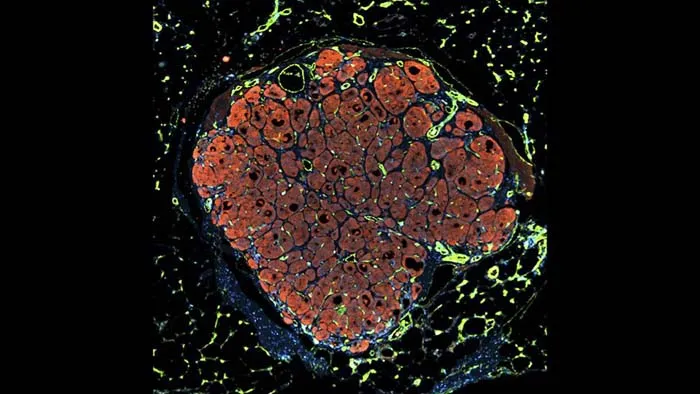

مهندسی بافت کبد انسان

این تکهی کوچک از کبد انسان درون بدن یک موش با کبد آسیبدیده گذاشته شده است. کبد انسان به کمک خون موش شروع به رشد کرده است.

سلولها در واکنش به آسیبدیدگی بافت میتوانند دوباره سازماندهی بیابند و درمان شوند و حتی رگهای خونی بسازند.

این تصویر با نمایش سلولهای کبد مهندسیشده پیام امید را منتقل میکند. همچنین این نوید را میدهد که با پیشرفت علم میتوان به مشکلات مربوط به جایگزینی اعضای بدن و بیماریهایی مثل سیروز یا سرطان کبد غلبه کرد.